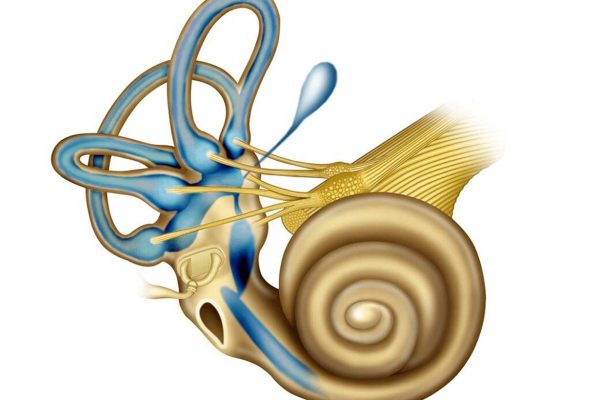

Três sistemas podem estar relacionados com estas patologias: sistema auditivo, sistema ocular e sistema propriocetivo. O sistema propriocetivo é um sistema extraordinariamente importante para o ser humano, que se inicia na planta do pé e veicula informações fundamentais até ao cérebro.

A todo o momento, olho direito, ouvido direito e metade direita do sistema propriocetivo estão a enviar informação para centros cerebrais de equilíbrio. Ao mesmo tempo a correspondente metade esquerda do corpo está a executar precisamente a mesma função através do envio para o cérebro de toda esta complexa informação.

O ouvido interno tem cristais de carbonato de cálcio ou otólitos ou otocónias, que contribuem para o equilíbrio e para os movimentos corporais normais. Quando estes otólitos se deslocam do seu local anatómico correto e migram para os chamados canais semicirculares dá a sensação que “tudo roda”.